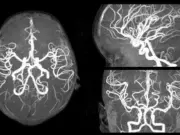

Виды МРТ головного мозга с сосудами

Магнитно-резонансная томография (МРТ) головного мозга является одним из самых точных методов диагностики заболеваний центральной нервной системы. Она позволяет получить детальные изображения структур головного мозга,...